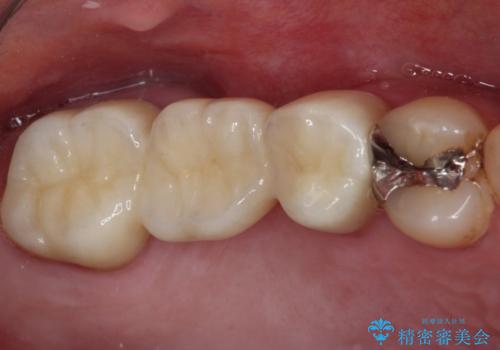

- 転んだ際に欠けてしまった前歯の変色が気になるとのことで来院された患者様です。

診察やレントゲン写真より神経組織の失活が認められたため、根管治療、ファイバーコアによる土台築製後、オールセラミッククラウンにて補綴することとしました。

神経を取り除いた歯は時間とともに変色してきます。

クリーニングやホワイトニングでは改善できないため、オールセラミッククラウンなどによる補綴治療が必要となります。